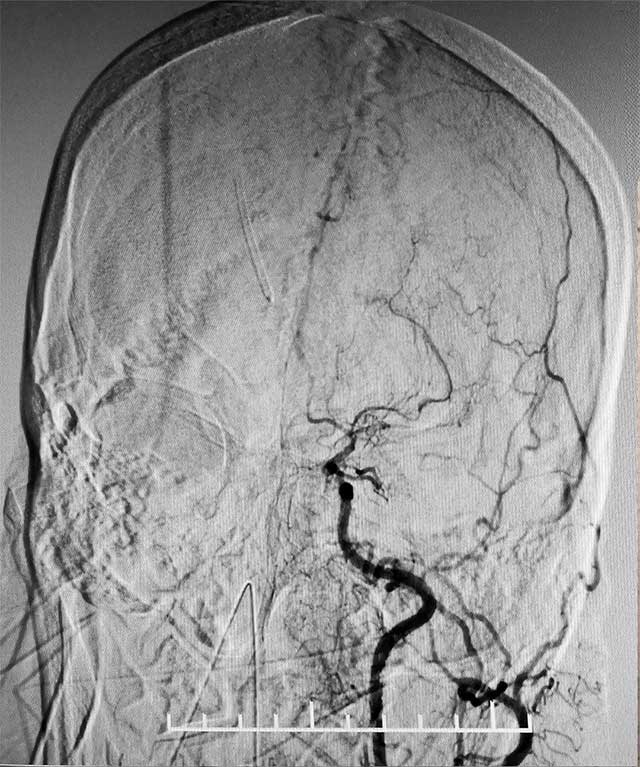

▲ 術(shù)前造影顯示,患者雙側(cè)頸內(nèi)動(dòng)脈末端閉塞,顱內(nèi)煙霧狀血管形成

患者是一位59歲女性,近一個(gè)月前,無明顯誘因出現(xiàn)惡心、噴射性嘔吐,隨即意識(shí)不清,送至當(dāng)?shù)蒯t(yī)院急診,行頭顱CT:腦室系統(tǒng)出血,立即于全麻下行腦室鉆孔引流術(shù)+儲(chǔ)液囊置入術(shù)。術(shù)后患者病情平穩(wěn)但神志嗜睡,處于淺昏迷狀態(tài)。

經(jīng)腦血管CTA和DSA檢查,結(jié)果顯示,患者雙側(cè)頸內(nèi)動(dòng)脈末端閉塞,左側(cè)大腦中動(dòng)脈閉塞,顱內(nèi)煙霧狀血管形成,左側(cè)顳頂枕葉灌注不足明顯,顱底出現(xiàn)細(xì)如煙霧的代償血管網(wǎng)絡(luò),腦部供血嚴(yán)重不足。結(jié)合病史,患者部被確診為煙霧病,由于代償血管壁長期受到異常血流沖擊,形成動(dòng)脈瘤導(dǎo)致腦出血。張琪博士決定為其實(shí)施復(fù)合手術(shù)室下顱內(nèi)外血管搭橋聯(lián)合硬腦膜翻手術(shù)。由于患者腦血流非常薄弱,任何風(fēng)吹草動(dòng),都有可能出現(xiàn)腦梗、腦出血。另外,在手術(shù)過程中,在全身麻醉狀態(tài)下,可能出現(xiàn)血壓降低,造成腦梗。所有這些無疑增加了手術(shù)難度和風(fēng)險(xiǎn)。